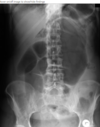

What is seen on AXR of baby with duodenal atresia?

Double bubble